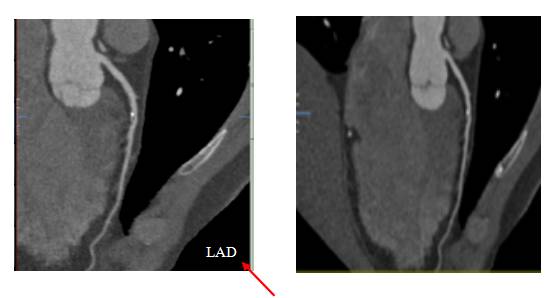

■ 曲面重建(CPR)

CPR是将弯曲走形的冠状动脉以官腔为中心进行多角度切面,同一根血管一般展示2-3个图像,主要是因为很多时候斑块都是偏心生长,一个切面不能反映斑块的实际情况。同一病变在不同切面上表现狭窄程度不同,以狭窄程度最重的切面为准。

在CPR图像中,图像上都会有指定的血管标注,比如标注前降支(LAD)就是告诉我们应该在这张图像上观察前降支血管,而非标注血管是不需要观察的。